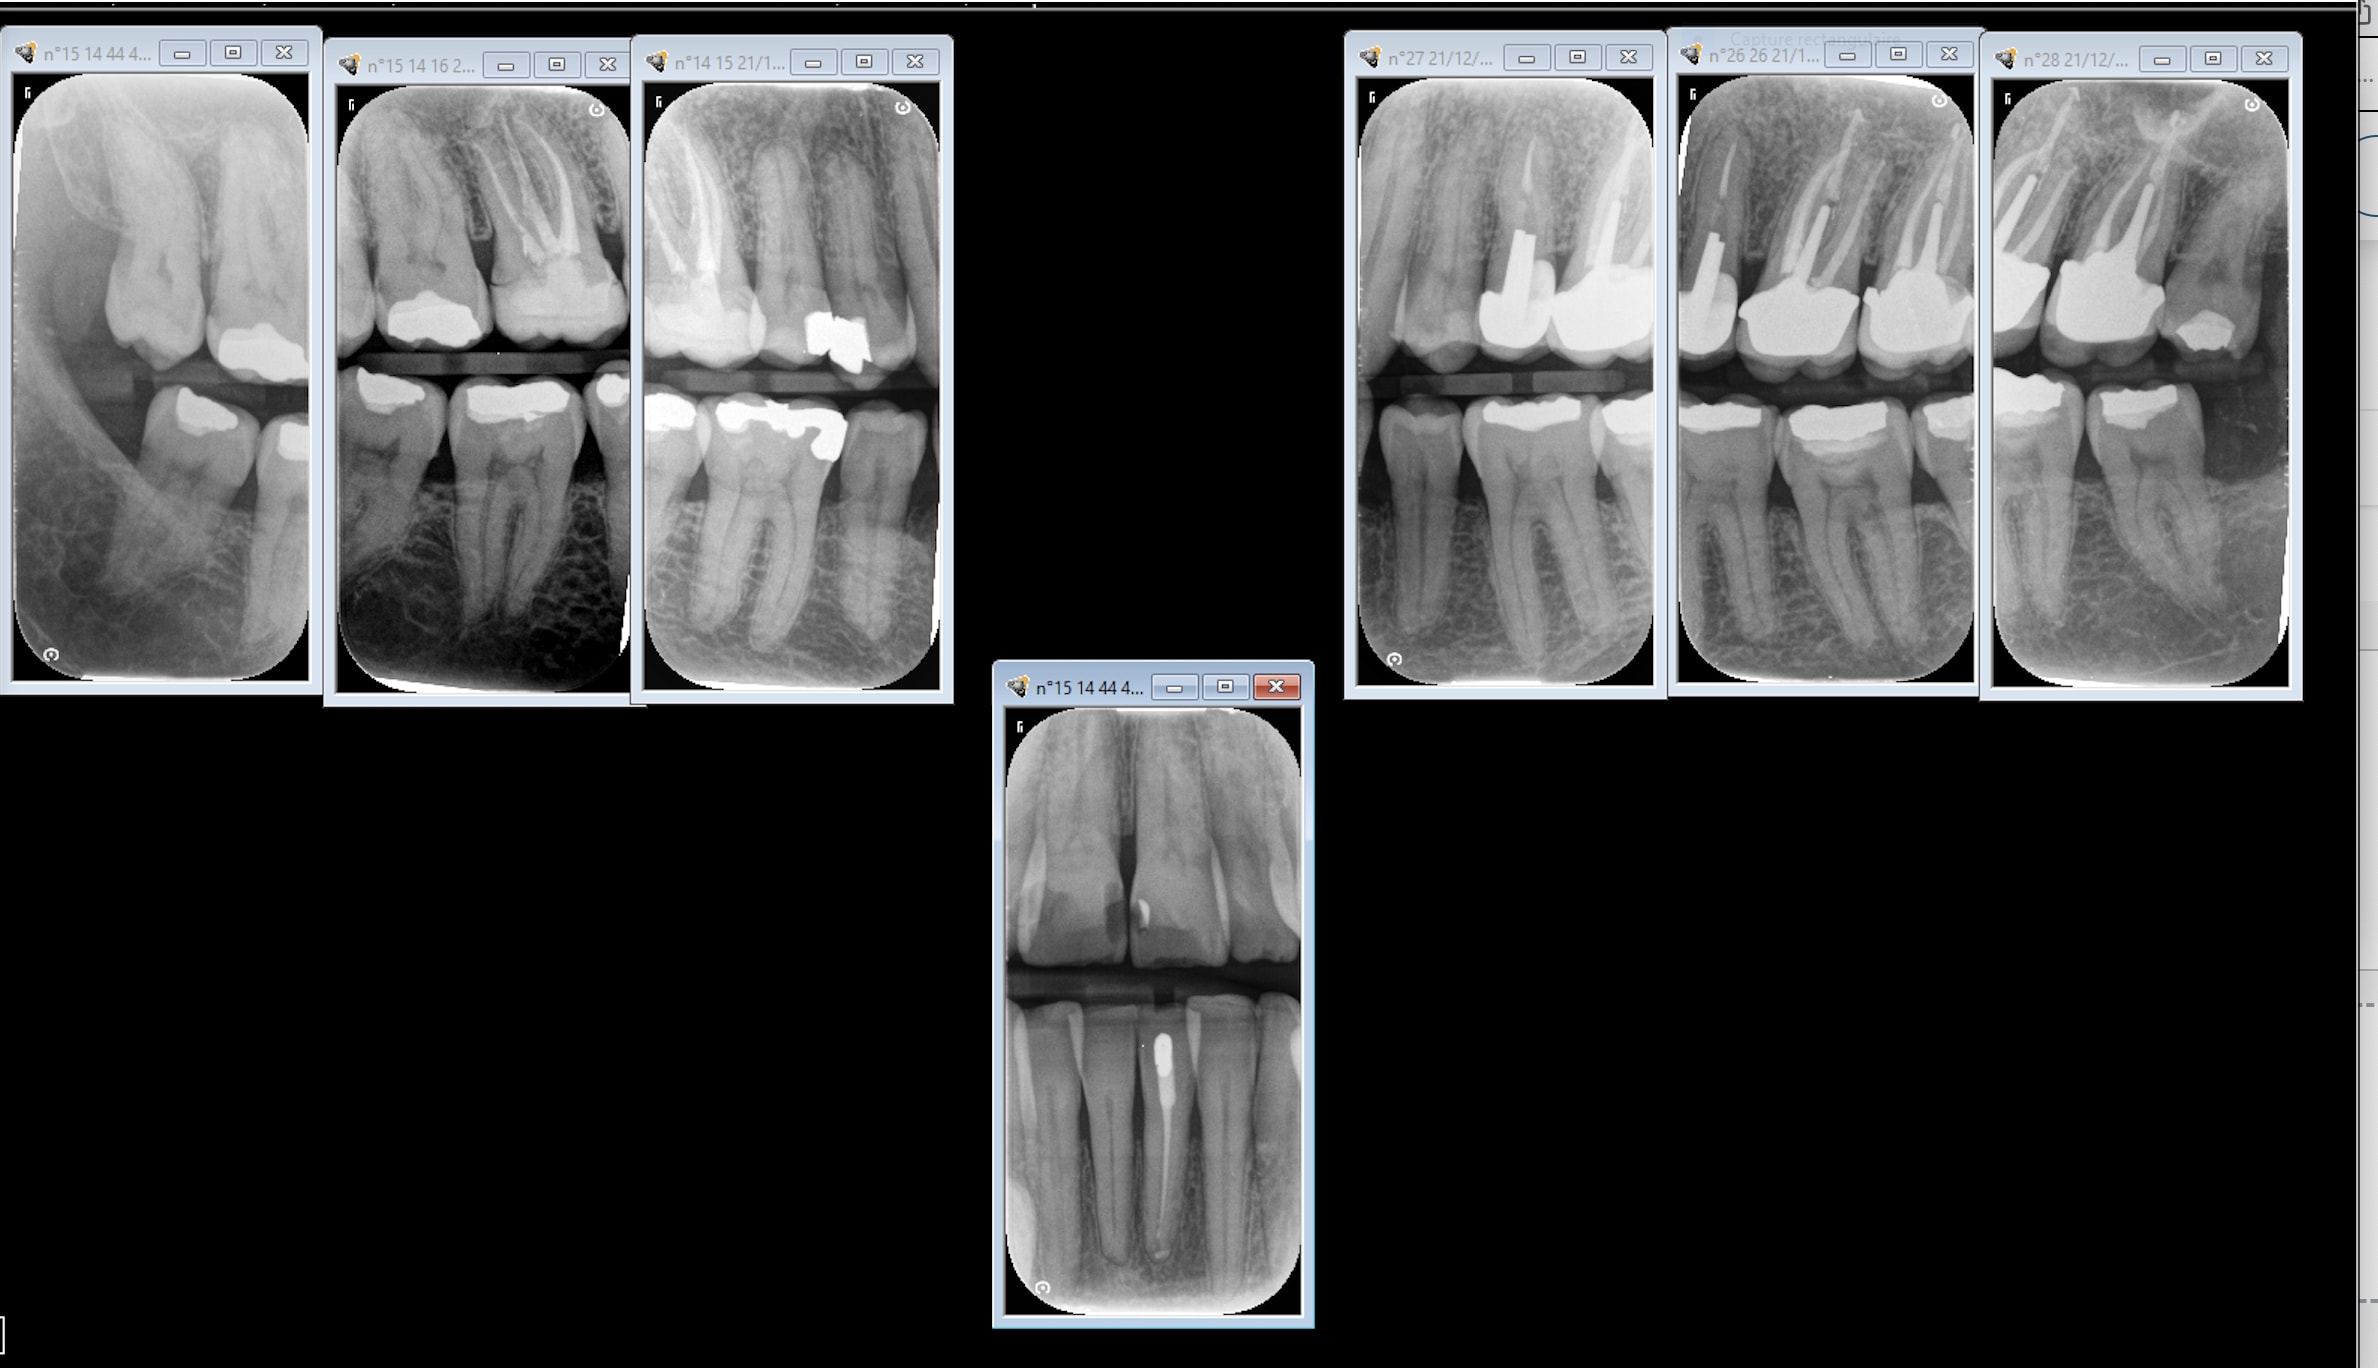

je veux savoir si c'est possible coter panoramique et bitewings dans le même rendez-vous dès lors que les deux techniques ont des objectifs différents.

aussi quand tu cotes les bitewings et que tu fais des molaires gauches, des prémolaires gauches, des molaires droites, des prémolaires droites, ça compte pour 4 rx ou 8 ? puisque tu fais 8 secteurs...

Très difficile d'obtenir de 7 (face distale) à 4 (face mésiale) sur des intra-buccales (rétro-coronaire comme rétro-alvéolaire) avec un capteur #1. Donc, pour des rétro-coronaires, il suffit de faire et de coter 7 et 4 de chaque coté pour avoir ses quatre radios.

Personnellement, je préfère les rétro-alvéolaires aux rétro-coronaires. Je trouve les premières beaucoup plus lisibles. Avec un bon angulateur (XCP de Dentsply) et un capteur RVG, ça prend trente secondes par radiographie.

je fait bitewings dans les molaires e premolaire donc 4 rx mais dans la logique des secteurs sont 4 radios 8 secteurs...

Si t'es syndiqué: 2 bitewing = 4 secteurs

La cnsd avait fait une conférence il ya qq années pour expliquer comment coter avec la nouvelle CCAM, et ils expliquaient tres clairement que pour eux 2 bitewing = 4 secteurs.

Donc quand je fais 2 bitewing, j'ai bien les radiographies intrabuccales rétrocoronaires de 4 secteurs distincts de 1 à 3 dents contigües

en ce cas j'avais raison... normalement je fait 4 bitewings et je cote 8 secteurs..

en plus une pano jamais te vas donner des info sufisants, principalement dans la region de les premolaires. et la % de patiente avec des caries de contact que sont pas visibles dans les pano c'est fou.

pour moi rdv de 1 fois i faut un bon diagnostique pour avoir le max de info avant d'avancer pour le plan de traitment.